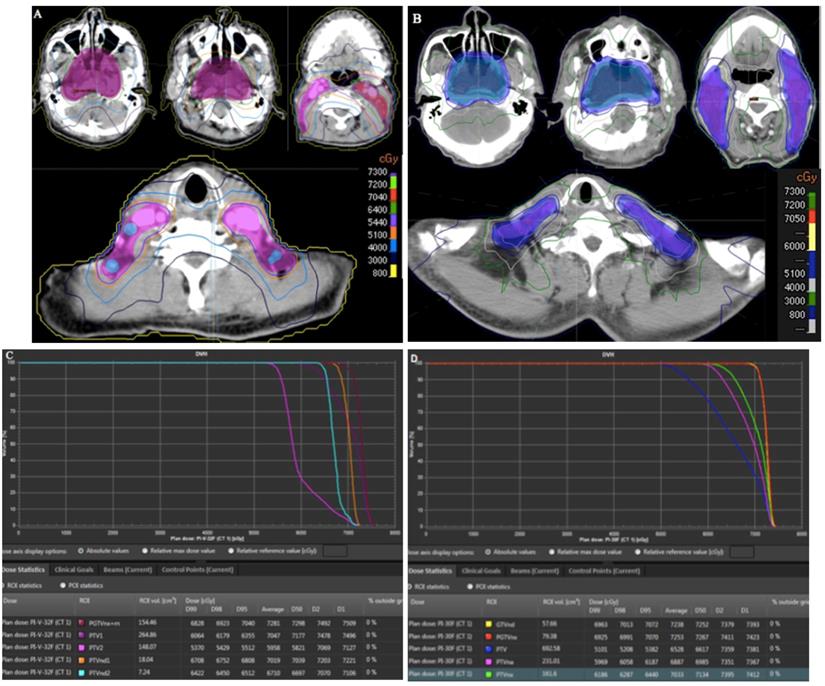

To illustrate our protocol of different risk target volumes, a histology-proven NPC patient was used to describe the different risk target volumes and the corresponding doses in IMRT planning. The MRI of this patient indicated that the primary tumor had invaded the parapharyngeal space, bilateral metastatic RLNs had occurred, and multiple metastatic lymph nodes were observed in the bilateral cervical and supraclavicular regions (Figure 5A). Therefore, the stage was T2N3M0. The patient received three cycles of TP-based IC. After CT simulation following the third IC, we delineated three risk target volumes including high-risk PGTVnx and GTVnd, intermediate-risk PTVnx and PTVna, and low-risk PTV. The IMRT planning was designed by an experienced physicist. Dose distribution was even (Figure 5B). The DVH showed that the prescribed doses met our requirements (Figure 5C).

Figure 5

Target volumes and IMRT planning in a patient with stage T2N3M0 NPC. (A) MRI of the patient; (B) different risk target volumes and dose distributions; (C) DVH of IMRT. Abbreviations: IMRT: intensity-modulated radiotherapy; NPC: nasopharyngeal cancer; MRI, magnetic resonance imaging; DVH: dose-volume histogram.

To evaluate the dosimetric benefits of our protocol, we selected two patients with T4-stage NPC. Target volumes for one patient were delineated using the China protocol, and our protocol was used for the other patient. In the China protocol, doses of 70.4, 70.4, 64, 60.8, and 54.4 Gy in 32 fractions were administered to PGTVnx+rn, PGTVnd1, PGTVns2, PTV1, and PTV2, respectively, while doses of 70.5, 70.5, 63, 60, and 51 Gy in 30 fractions were administered to PGTVnx, PGTVnd, PTVnx, PTVna, and PTV. The two IMRT plans met the requirements. Compared with the China protocol, our strategy led to reductions in the V40 and V30 (Figure 5A and 5B) and D2 and D1 (Figure 6C and Figure 6D). For the three risk target volumes, the high dose was more concentrated in the GTV, and the area receiving a low dose was decreased.

Figure 6

Comparison of target volumes and dose distributions between two protocols. (A) target volumes and dose distributions of the China protocol; (B) target volumes and dose distributions of our protocol; (C) DVH of the China protocol; (D) DVH of our protocol. Abbreviation: DVH: dose-volume histogram.